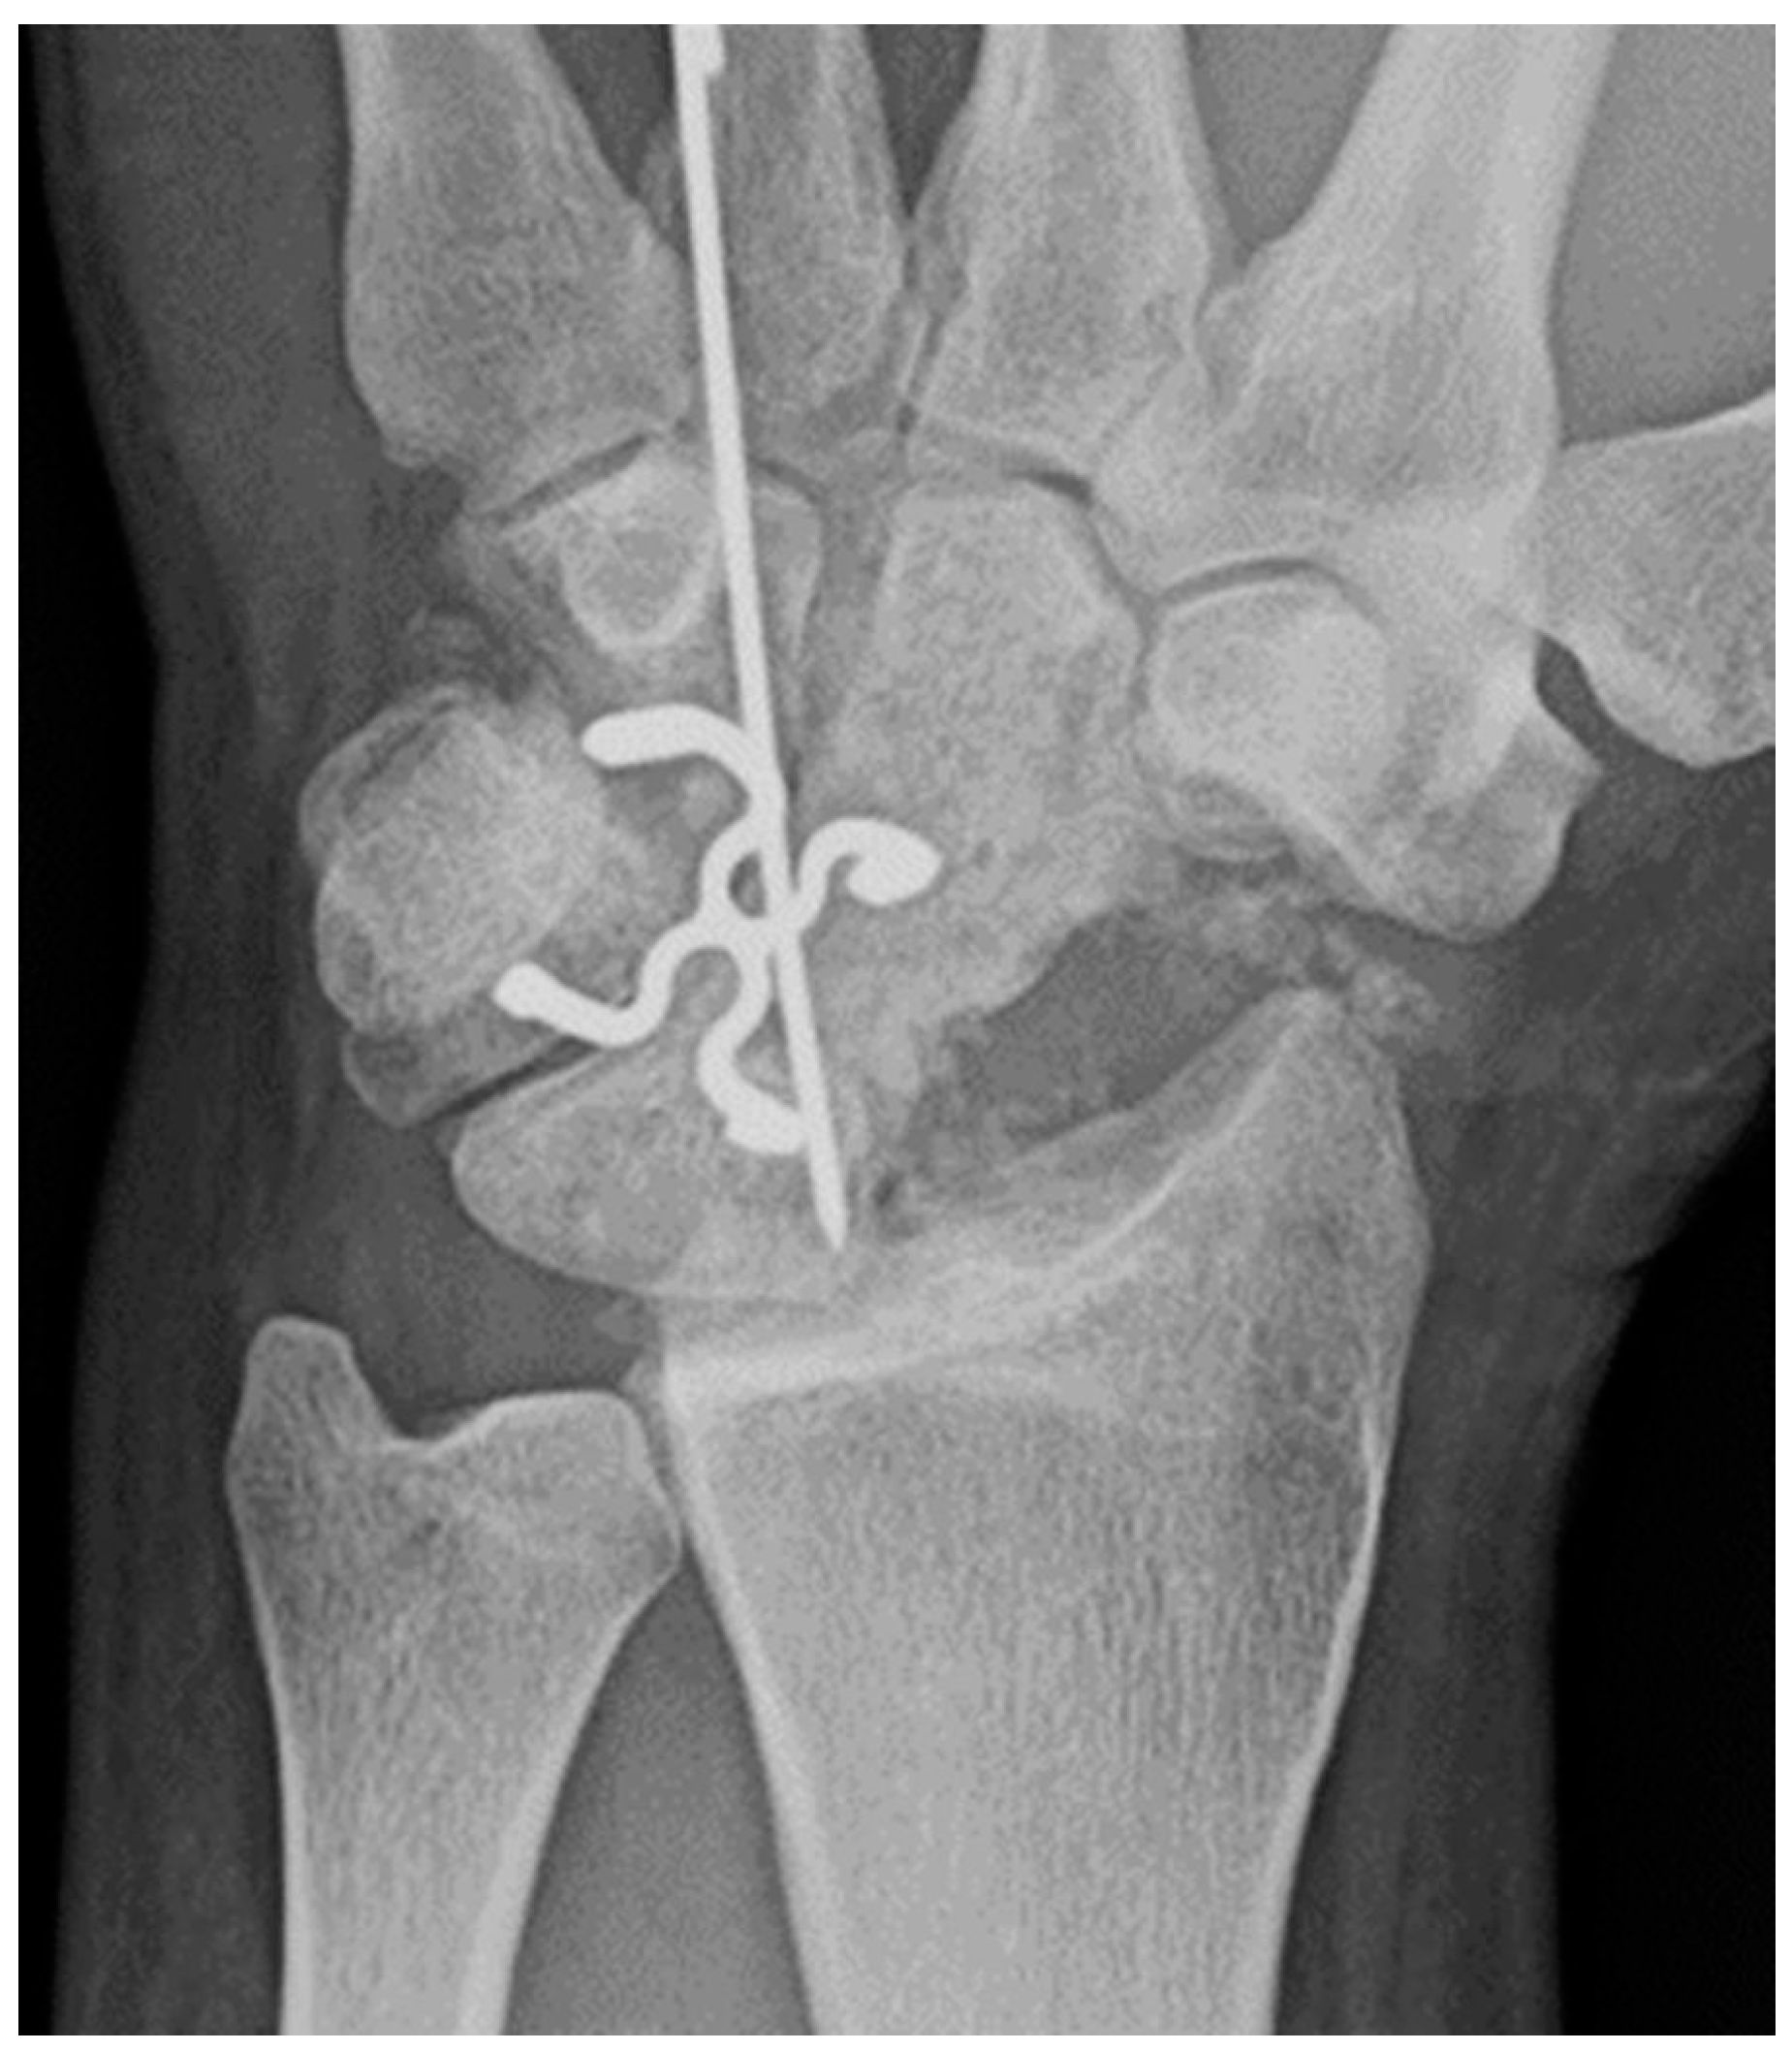

Common scaphoid fracture complications include avascular necrosis and nonunion [10]. Avascular necrosis is a dreaded outcome resulting from loss of the proximal arterial supply due to the distal entry point of nutrient vessels. This retrograde perfusion of the proximal pole makes it vulnerable to losing its vascular supply when fractured. Sclerosis of the proximal pole indicates osteonecrosis (Figure 5). With scaphoid nonunion, biomechanical alterations contribute to rapidly progressive degenerative arthritis and instability referred to as scaphoid nonunion advanced collapse (SNAC) [16]. Nonunion occurs in 5-10% of cases and has a higher incidence with displaced fractures (Figure 6). During wrist extension, the distal scaphoid fragment rotates into flexion while the proximal scaphoid fragment extends with the lunate. The resultant abnormal contact between the distal fragment and radius begins the first stage in degenerative collapse. This progresses into the second stage as scaphocapitate osteoarthritis develops and finally to the third stage with progression to capitolunate osteoarthritis and proximal radial migration of the capitate dorsal to the lunate. Treatment of SNAC wrists, depending on the degree and severity of the osteoarthritic collapse include scaphoidectomy with four-corner arthrodesis or wrist fusion [17]. Four-corner fusion helps reduce joint pain while maintaining some range of motion, as opposed to total wrist fusion (Figure 7).

Figure 7. Four corner fusion with scaphoidectomy and surgical staple fusion of the lunate, capitate, hamate, and triquetrum with temporary Kirschner wire fixation.